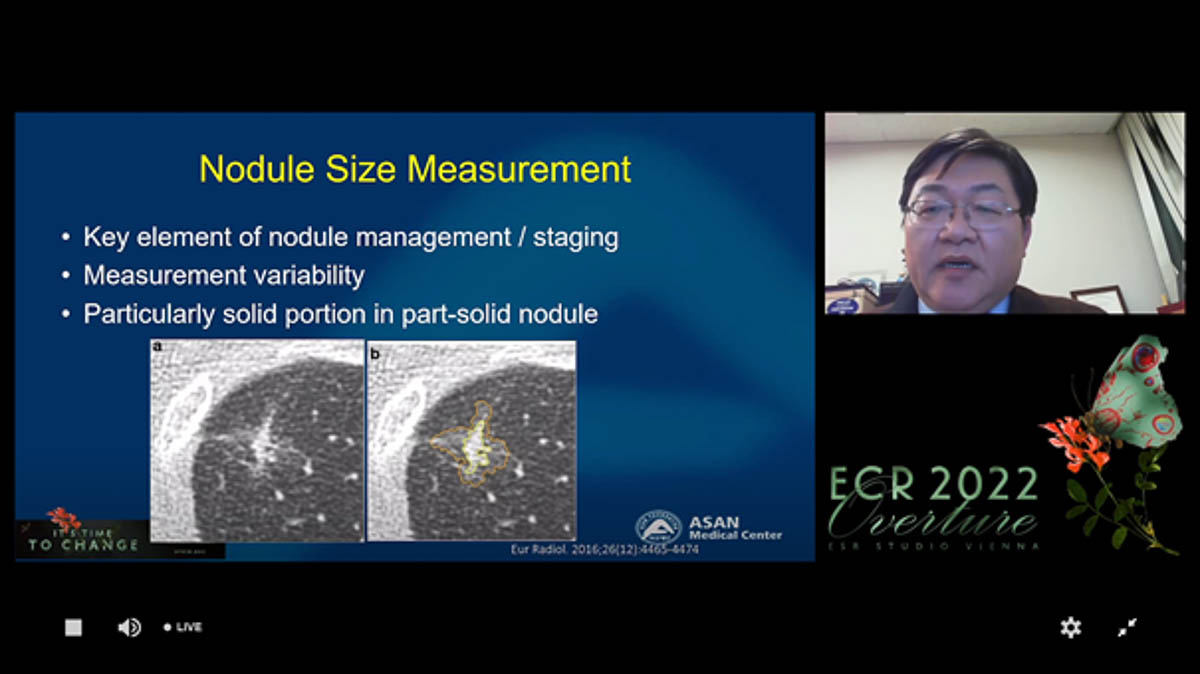

Le 3 mars dernier, une session de l’ECR sur les avancées technologiques en imagerie thoracique s’intéressait à la transition de la recherche à la pratique. Concernant l’intelligence artificielle, Joon Beom Seo, radiologue au centre hospitalier Asan à Séoul (Corée du sud) s'est demandé comment l’IA pouvait améliorer les pratiques dans l’imagerie du cancer du poumon. « L’IA pourrait s’appliquer à la détection des nodules en contexte de dépistage, au diagnostic du cancer et à la stadification, à la prédiction de la réponse au traitement et du risque de récidive, avance Joon Beom Seo. Elle peut être utilisée quasiment à chaque étape de l’imagerie du cancer pulmonaire. »

Toutefois, les logiciels commercialisés se limitent pour le moment à la détection et la caractérisation des nodules. Douze solutions d’IA sont actuellement disponibles sur le marché (marquées CE et FDA) pour la détection des nodules pulmonaires au scanner, précise l'intervenant. Mais la détection